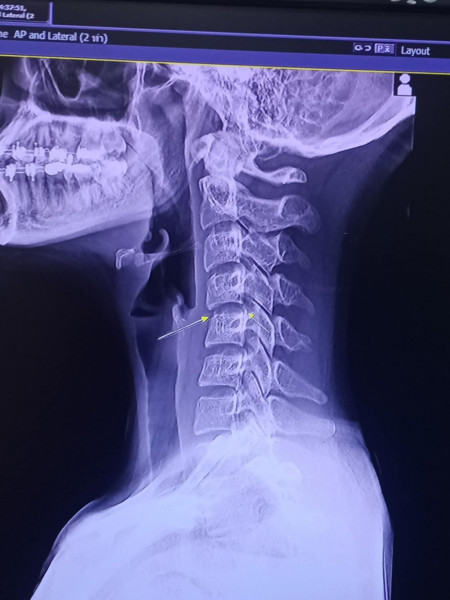

Chayada就醫後,醫生告知她原因頸椎早已受傷,接受按摩後更致神經受損,演變至半身癱瘓。她曾在Facebook透露自己的狀況和心情稱,「我想回覆大家的留言,但是我不能動,被困在床上」、「我想站起來跳舞,我很沮喪」。據泰媒報道,Chayada於12月8日離世,死於與血管感染和腦部腫脹有關的併發症。

按摩後導致中風、癱瘓的新聞時有發生,泰式按摩或肩頸按摩真的如此危險和致命?腦神經外科醫生黃秉康接受《星島頭條》訪問指,「lock頸」直接扭斷頸部神經線或引致癱瘓的機會較微,反而應該擔心傷及頸部血管。

他表示,頸部有4條血管供血給大腦,當頸部急劇扭動或創傷,可能引發以下情況:

- 導致血管撕裂,血管內壁受損,有機會形成血塊。

- 若血塊跟隨血液流上腦,可能造成血管閉塞,甚至即刻阻塞血管,引致腦部受損或神經受損問題。

- 當腦部受損或者中風,的確有機會令腦細胞出現水腫或有感染的併發症。